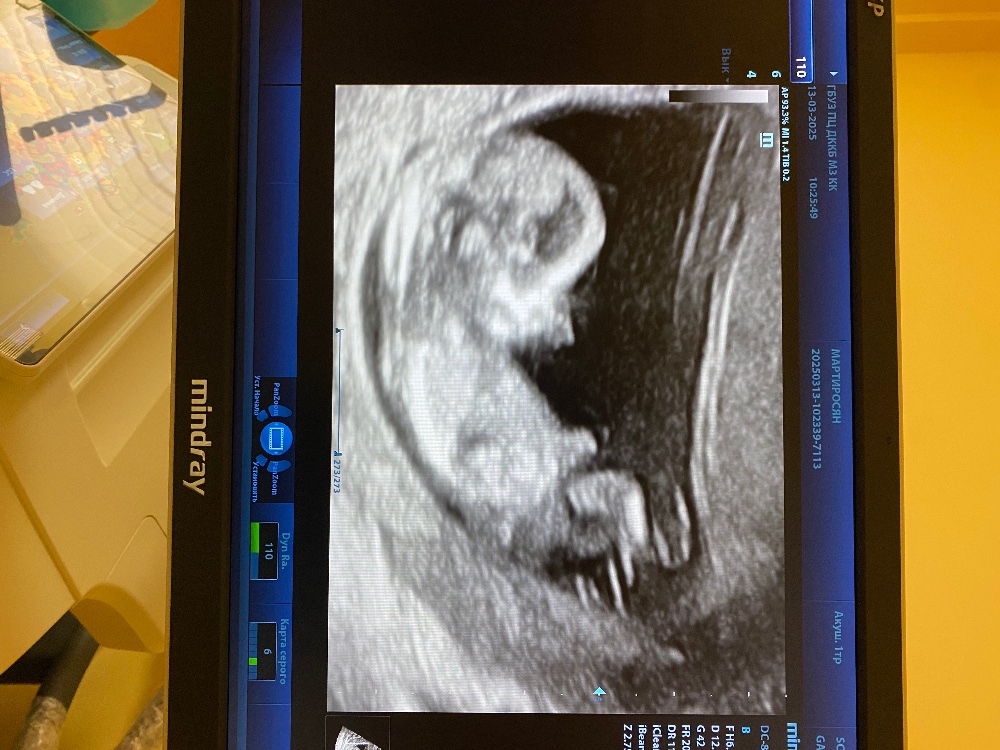

Пол по первому скринингу

То, что торчит вверх - это пуповина, скорее всего. Полового бугорка на фото не видно, соответственно пол не предположить.

Очень люблю участвовать в гадалках. Но это пуповина. По пуповине я не понимаю😂😂😂

Мимимишность фото зашкаливает.💕 , думаю что мальчик))

Это мальчик скорее всего

Мне кажется , девочка Там если ниже пуповины приблизить, то вроде бы еле видно бугорок , направленный вниз